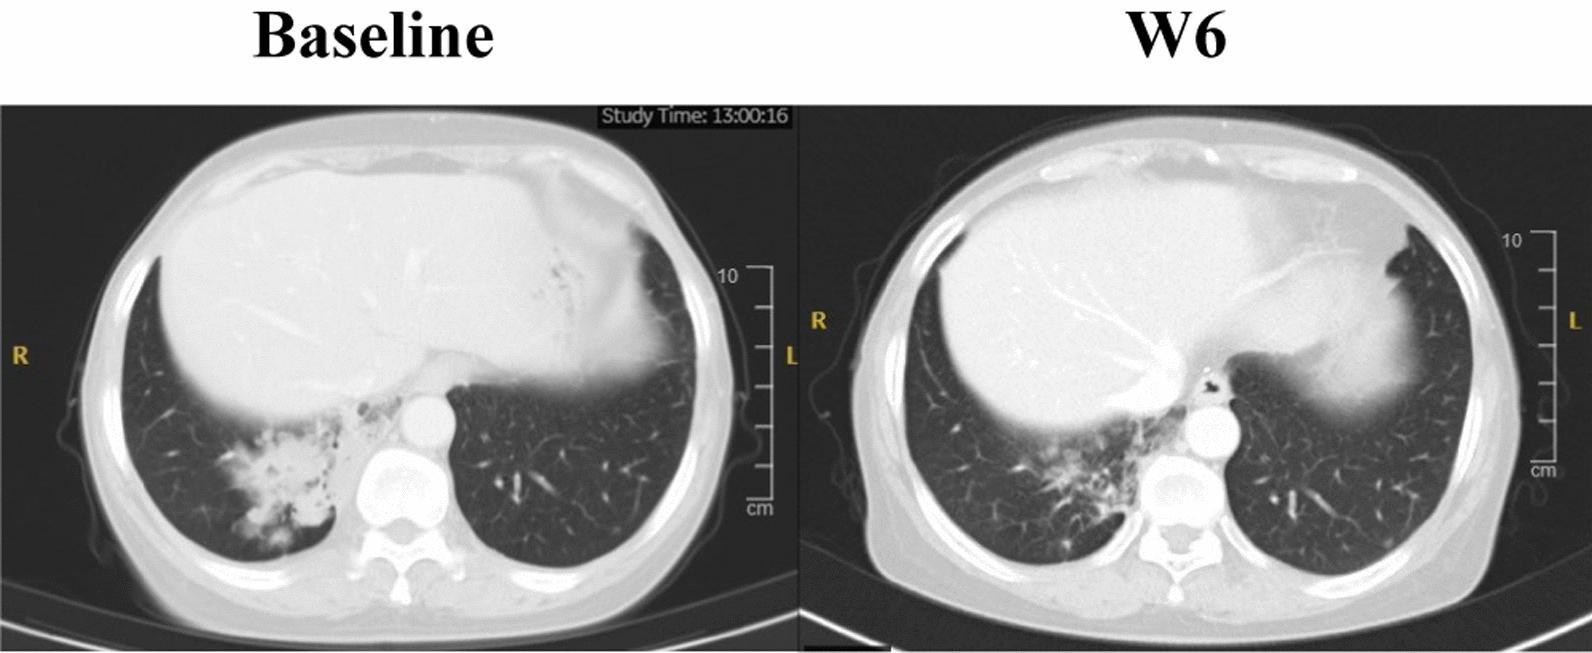

HS-10375 showed more potent activity in inhibiting EGFR phosphorylation compared to 1st to 3rd generation EGFR TKIs in C797S triple-mutant cell lines. HS-10375 also exhibited comparable inhibitory activity to 1st- and 2nd- generation EGFR TKIs and superior activity to 3rd-generation EGFR TKIs in C797S double-mutant cell lines. Furthermore, cells harboring EGFR double or triple C797S mutation underwent remarkable apoptosis upon HS-10375 treatment. HS-10375 effectively inhibited tumor growth in C797S triple-mutant mouse models. In the first-in-human trial, 28 patients with advanced or metastatic non-small cell lung cancers who harbored EGFR mutation and who had experienced treatment failure with EGFR TKI treatment received at least one dose of HS-10375. Dose-limiting toxicities were observed in 2 patients at 240 mg QD, and MTD was reached at HS-10375 150 mg QD. The most common treatment-related adverse events were vomit (37.0%), loss of appetite (33.3%), and elevated AST (33.3%). One patient with EGFR mutations showed tumor shrinkage after progression on five-line treatment including gefitinib, almonertinib, chemotherapy, immunotherapy, and EGFRxHER3 antibody-drug conjugate.

在C797S三重突变细胞系中,与第一代至第三代EGFR TKIs相比,HS-10375在抑制EGFR磷酸化方面表现出更强的活性。在C797S双突变细胞系中,HS-10375还表现出与第一代和第二代EGFR TKIs相当的抑制活性,且优于第三代EGFR TKIs。此外,携带EGFR双或三重C797S突变的细胞在HS-10375处理后发生显著凋亡。HS-10375有效抑制了C797S三重突变小鼠模型中的肿瘤生长。在首例人体试验中,28例携带EGFR突变且EGFR TKI治疗失败的晚期或转移性非小细胞肺癌患者接受了至少一剂HS-10375。在240毫克QD剂量下,2例患者出现剂量限制性毒性,HS-10375 150毫克QD达到MTD。最常见的治疗相关不良事件为呕吐(37.0%)、食欲减退(33.3%)和AST升高(33.3%)。1例EGFR突变患者在接受包括吉非替尼、阿美替尼、化疗、免疫治疗和EGFRxHER3抗体药物偶联物在内的五线治疗进展后出现肿瘤缩小。